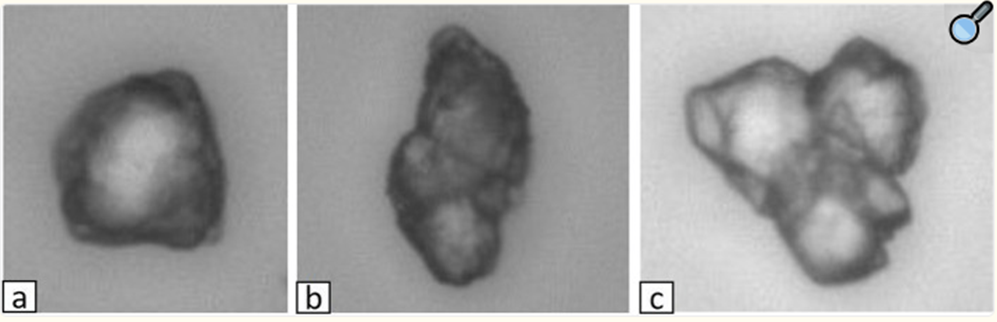

EBIR-20D :

PEO 기반

Gel-beads